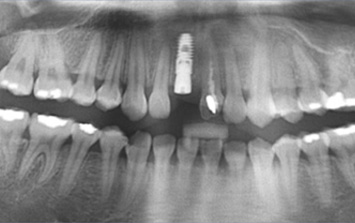

왼쪽 어금니 상실로 내원한 환자분. 위 턱뼈의 경우 아래턱뼈보다 얇고 상악동 있어 임플란트를 실패할 가능성이 높습니다.

턱뼈의 해부학적 구조를 충분히 고려한 상악동 뼈이식 후 임플란트를 식립하였습니다.